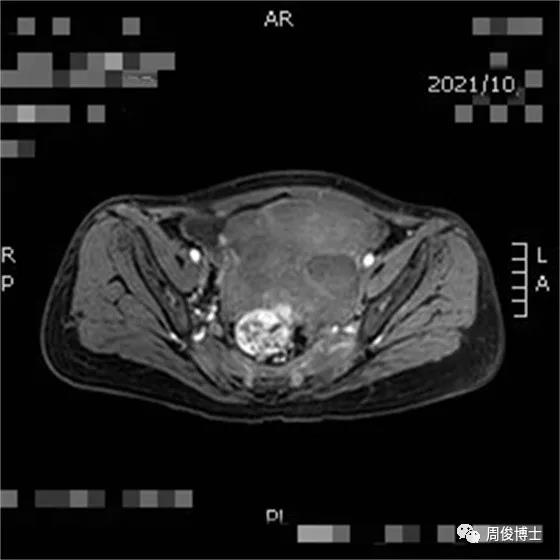

治療七個月后,腫瘤繼續(xù)縮小,腸道通暢,子宮大小恢復(fù)正常,肌肉脂肪豐滿

這樣一個終末期的胃癌,還是經(jīng)過現(xiàn)有醫(yī)療上的多種藥物治療失敗的,沒有細胞治療,是不可能出現(xiàn)病情逆轉(zhuǎn)、恢復(fù)正常生活的,讓我們一起來贊美科學(xué)家、感謝臨床研究者,更要祝福勇于參加臨床研究的受試者和家屬,是他們?yōu)獒t(yī)學(xué)事業(yè)作出的貢獻,造福更多的腫瘤患者,共筑人類命運共同體。